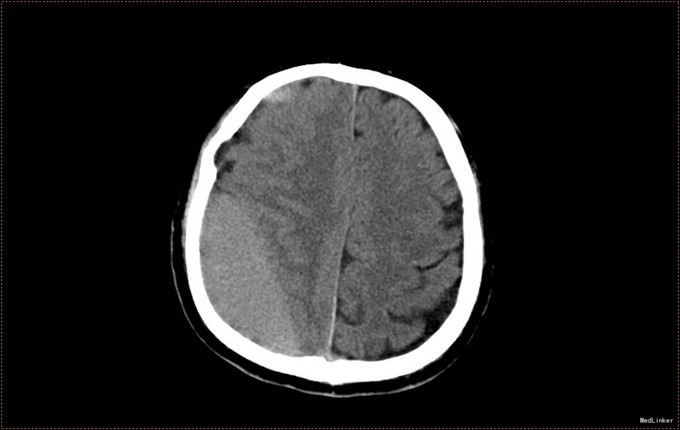

患者,男,53岁。以“左侧肢体疼痛伴无力1周”为主诉入院。患者1周前无明显诱因出现左侧肢体无力,伴酸痛,头部闷胀感,症状持续不缓解,于我院就诊,行头部CT及MR提示右侧顶枕叶硬膜下血肿。右侧额颞叶蛛网膜囊肿。患者为求进一步治疗,急诊以“硬膜下血肿”为诊断,收入病房。患者病来精神状态差,饮食睡眠可,二便可,体重无明显变化。否认近期头部外伤史。

入院查体:T:36.5℃ ,P:68次/分 ,BP:130/80mmHg , R:16次/分。步入病房,自主体位。神清语明,问答准确,查体合作,精神状态良好,定向力完整。粗测视野正常,双侧瞳孔等大正圆,D≈3.0mm,双侧眼球活动自如,对光反射灵敏。四肢活动自如,左侧肢体肌力V-级,右侧肢体肌力Ⅴ级,肌张力正常。深浅感觉检查未见异常。头CT及MR提示右侧颞极蛛网膜囊肿,右侧亚急性硬膜下血肿

患者诊断明确,完善术前检查行局麻右侧钻孔冲洗引流术,予常规治疗。术后3天拔管,复查头CT硬膜下血肿消失,但脑组织膨胀不良。患者左侧肢体肌力恢复正常,无头晕头沉症状,顺利出院。